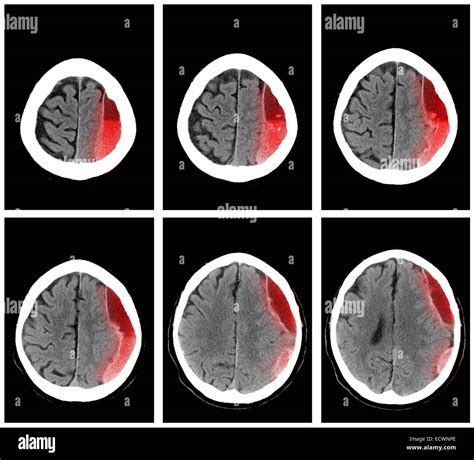

Subdural hemorrhage is a serious medical condition that requires immediate attention. It occurs when blood collects between the dura mater and the arachnoid mater, the two outermost membranes that cover the brain. Early and accurate diagnosis is crucial for effective treatment, and one of the most reliable methods for diagnosing subdural hemorrhage is through the use of Subdural Hemorrhage CT Images.

Computed Tomography (CT) scans are the gold standard for diagnosing subdural hemorrhage. CT scans provide detailed Subdural Hemorrhage CT Images that help radiologists and neurologists identify the presence and extent of the hemorrhage. These images are crucial for determining the appropriate course of treatment.

CT scans use X-rays to create cross-sectional images of the body. In the case of subdural hemorrhage, the CT scan focuses on the brain to detect any abnormalities. The images produced are highly detailed and can show the exact location and size of the hemorrhage. This information is essential for planning surgical interventions if necessary.

Interpreting Subdural Hemorrhage CT Images

Interpreting Subdural Hemorrhage CT Images requires a trained eye. Radiologists look for specific signs that indicate the presence of a subdural hemorrhage. These signs include:

• Hyperdense crescent-shaped collections of blood between the skull and the brain.

• Midline shift, where the brain is pushed to one side due to the pressure from the hemorrhage.

• Effacement of the sulci and ventricles, indicating compression of the brain tissue.

These findings help in diagnosing the type and severity of the subdural hemorrhage.

• Acute Subdural Hemorrhage: Occurs within 72 hours of the injury and appears as a hyperdense collection on CT images.

• Subacute Subdural Hemorrhage: Occurs between 3 to 20 days after the injury and may appear isodense or hypodense on CT images.

• Chronic Subdural Hemorrhage: Occurs more than 20 days after the injury and appears hypodense on CT images.